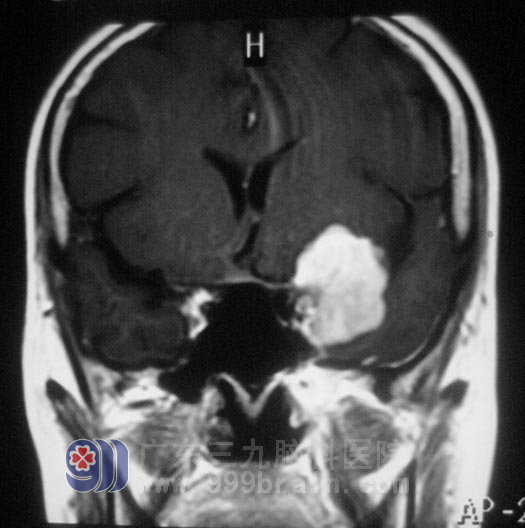

颈椎MR提示“颈4/5、5/6、6/7椎间盘突出”,头颅MR示“左侧蝶骨嵴脑膜瘤,大小约2.8cm×2.9cm×3.1cm”。家人回想起两年前,黄女士就开始出现左眼视力下降,偶有头晕,并没有引起重视,知道这个结果后肠子都悔青了。

11月23日,由广东三九脑科医院综合神经外科 鲁明主任主刀,在全麻下行左侧蝶骨嵴脑膜瘤切除术+颅内压探头植入术,术中取左侧额颞弧形切口,在显微镜下见肿瘤呈灰白色,与大脑中动脉粘连紧密,予肿瘤全切,对视神经、动眼神经保护完好。术后黄女士经过一段时间的恢复,诉左眼视力较术前明显好转,肩周炎也在广东三九脑科医院得到了有效的治疗。术后病理结果:过渡型脑膜瘤 WHO I 级。http://www.999brain.com/